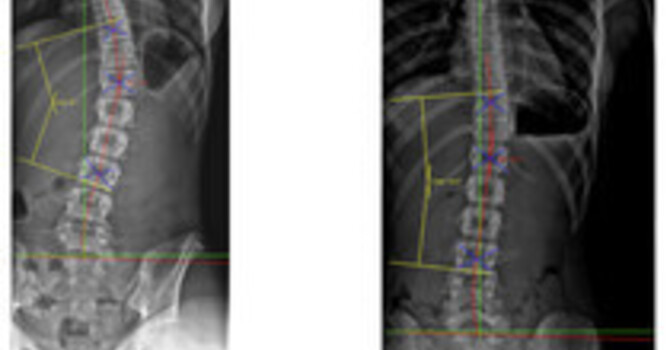

One of the central challenges with whiplash injuries is that they often do not present with obvious structural damage on standard X-ray or MRI imaging. This has led to the mistaken assumption—frequently echoed by insurance carriers—that symptoms must therefore be muscular or self-limiting. However, decades of biomechanical research demonstrate that whiplash is primarily a soft tissue injury involving ligaments, joint capsules, and disc structures, particularly in the upper and mid-cervical spine. Muscles are rarely the primary pain generator, and that distinction matters when determining both prognosis and treatment.

Understanding these mechanisms is not academic—it directly informs how we document injuries, educate patients, and design care plans. In my work at Clear Life Scoliosis in the Charlotte, North Carolina area, careful attention to cervical alignment, segmental motion, and ligament integrity is essential, particularly in patients who present weeks or months after a collision. When these injuries are recognized early and managed appropriately, outcomes improve. When they are dismissed as “just muscle strain,” chronic pain becomes far more likely.